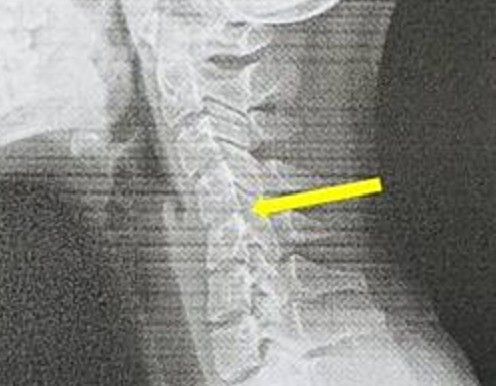

近日一名20歲女大生因長期頭痛、頸部僵硬到求診,經X光檢查竟發現她的頸椎弧度完全消失,變成一條僵硬直線,甚至出現滑脫現象,退化程度宛如60歲老年人。神經內科主任葉宗勳診斷後直言,這就是典型的「手機頸」,與患者每天長時間低頭滑手機、躺床追劇的不良習慣密切相關。

員榮醫院神經內科主任葉宗勳醫師解釋,健康的頸椎應呈現自然的「C字形」弧度,就像天然避震器,能有效分散頭部重量和活動壓力。但這名女大生平時除了上課,幾乎手機不離手,經常躺在床上追劇看到睡著,長期不良姿勢導致頸椎承受巨大壓力,最終弧度消失、提前退化。